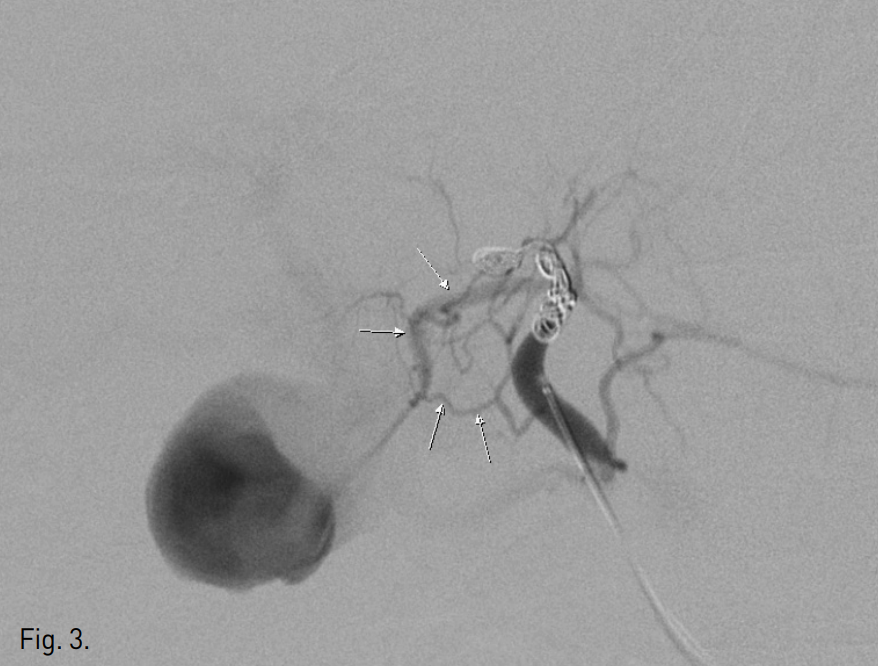

5F sheath를 우측 총대퇴동맥 내로 삽입한 후, 0.035 inch guide wire(Terumo, Tokyo, Japan)와 RH catheter(Cook, Bloomington, IN, USA)를 이용하여 총간동맥 혈관조영술을 시행함. 제 4 간분절로 가는 간동맥에서 기시하는 가성동맥류를 확인하고 0.014 inch Transcend guide wire(Boston scientific, Natick, MA, USA)와 2.2F Progreat microcatheter (Terumo, Tokyo, Japan)를 이용하여 superselection하여 4개의 tornado microcoil(Cook, Bloomington, IN, USA)과 gelatin sponge particle(gelfoa m)로 색전술을 시행함. 그러나 시술 후 시행한 혈관촬영술에서 처음에는 보이지 않던 간내 곁순환에 의해서 가성동맥류는 여전히 관찰됨(Fig. 3). 초음파 유도 하에 22G Chiba needle(A&A medical, Seoul, Korea)로 가성동맥류를 직접 천자하여 Yellow sheath(A&A medical, Seoul, Korea)를 삽입하고 1% sodium tetradecyl sulfate (Tromboject) 2 cc, N-butyl-2-cyanoacrylate(glue)(B. Braun, Melsungen AG, Germany)와 리피오돌 1:4 혼합액 4 cc로 색전술을 시행함(Fig. 4). 이 과정에서 우측 간동맥 전분절 분지내로 혼합액의 일부가 유입되었음. 다시 시행한 혈관 조영술에서 가성동맥류가 완전히 폐색된 것을 확인함 (Fig. 5).

Fig. 3

Middle hepatic angiography after the coil embolization shows opacification of the pseudoaneurysmal sac via in trahepatic collaterals (arrows).